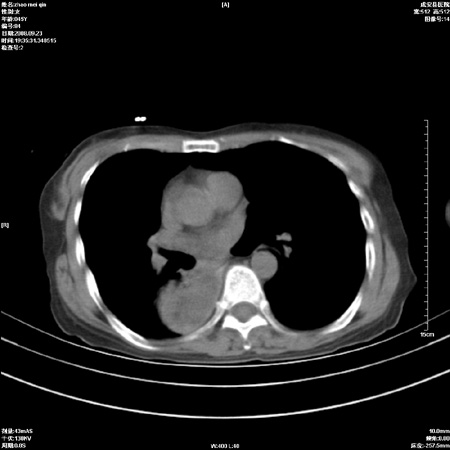

标题: CT15861:女 60 外伤后1小时 胸疼 [打印本页]

标题: CT15861:女 60 外伤后1小时 胸疼

外伤后1小时 胸疼 是外伤后引起的吗?

食道扩张明显下端逐渐变窄,倒像贲门失迟缓

未除外食道异物。如食道石长时间受阻。

不除外贲门占位梗阻

非外伤性改变,典型的贲门失迟缓症

食道扩张明显下端逐渐变窄,大量食物存留,象贲门失迟缓症。